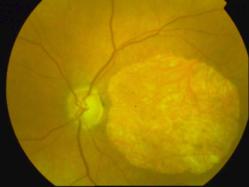

CICATRICE APRES EXERESE CHIRURGICALE DE NEOVAISSEAUX

IM000007.JPG